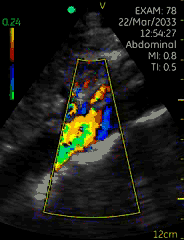

Vscan临床图片 腹部